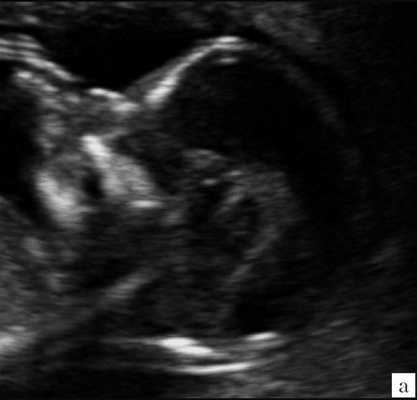

При изучении анатомии головного мозга плода в режиме 2D с применением стандартных аксиальных срезов во всех наших случаях мозжечок выглядел в виде овального образования однородной структуры с поперечным размером, менее уровня 5 процентиля для соответствующего срока беременности. При этом отсутствовала межполушарная выемка и область повышенной эхогенности по срединной линии мозжечка, характерная для отражения червя (рис. 1). На коронарном срезе также обращала внимание округлая однолобарная форма гипоэхогенного мозжечка (рис. 2). Использование трансвагинального подхода позволяло визуализировать дополнительно волокнистые структуры субарахноидального пространства (рис. 2).

Рис. 1. Аксиальные срезы головного мозга плода. Отражена картина однолобарного гипоплазированного мозжечка во всех наблюдениях.

а) Наблюдение 1.

б) Наблюдение 2.

в) Наблюдение 3.

г) Наблюдение 4.